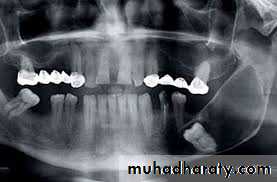

8- Supernumerary teeth :

The teeth maybe impacted or malposed and such teeth may predispose to malocclusion , periodontal disturbances, facial pain , bony pathology (cyst), esthetic problems and preventing the erupting on of teeth .9- Tooth in the fracture line of the jaws :